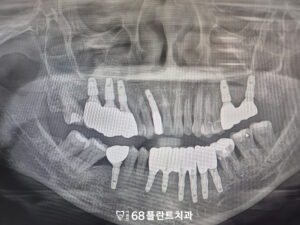

◆ 전 > 후 ◆

23.04.05 / 25.11.25

치료 마무리 후 사진입니다.

환자분께서는 치료 전

흔들리고 불편했던 치아로 인해

식사도 제대로 못하고 많이 힘들어하셨습니다.

그러나 현재는 임플란트 치료를 통해

안정적인 치아 기능을 회복하셨고,

식사나 일상 생활에서 불편함 없고

매우 만족해 주셨습니다.